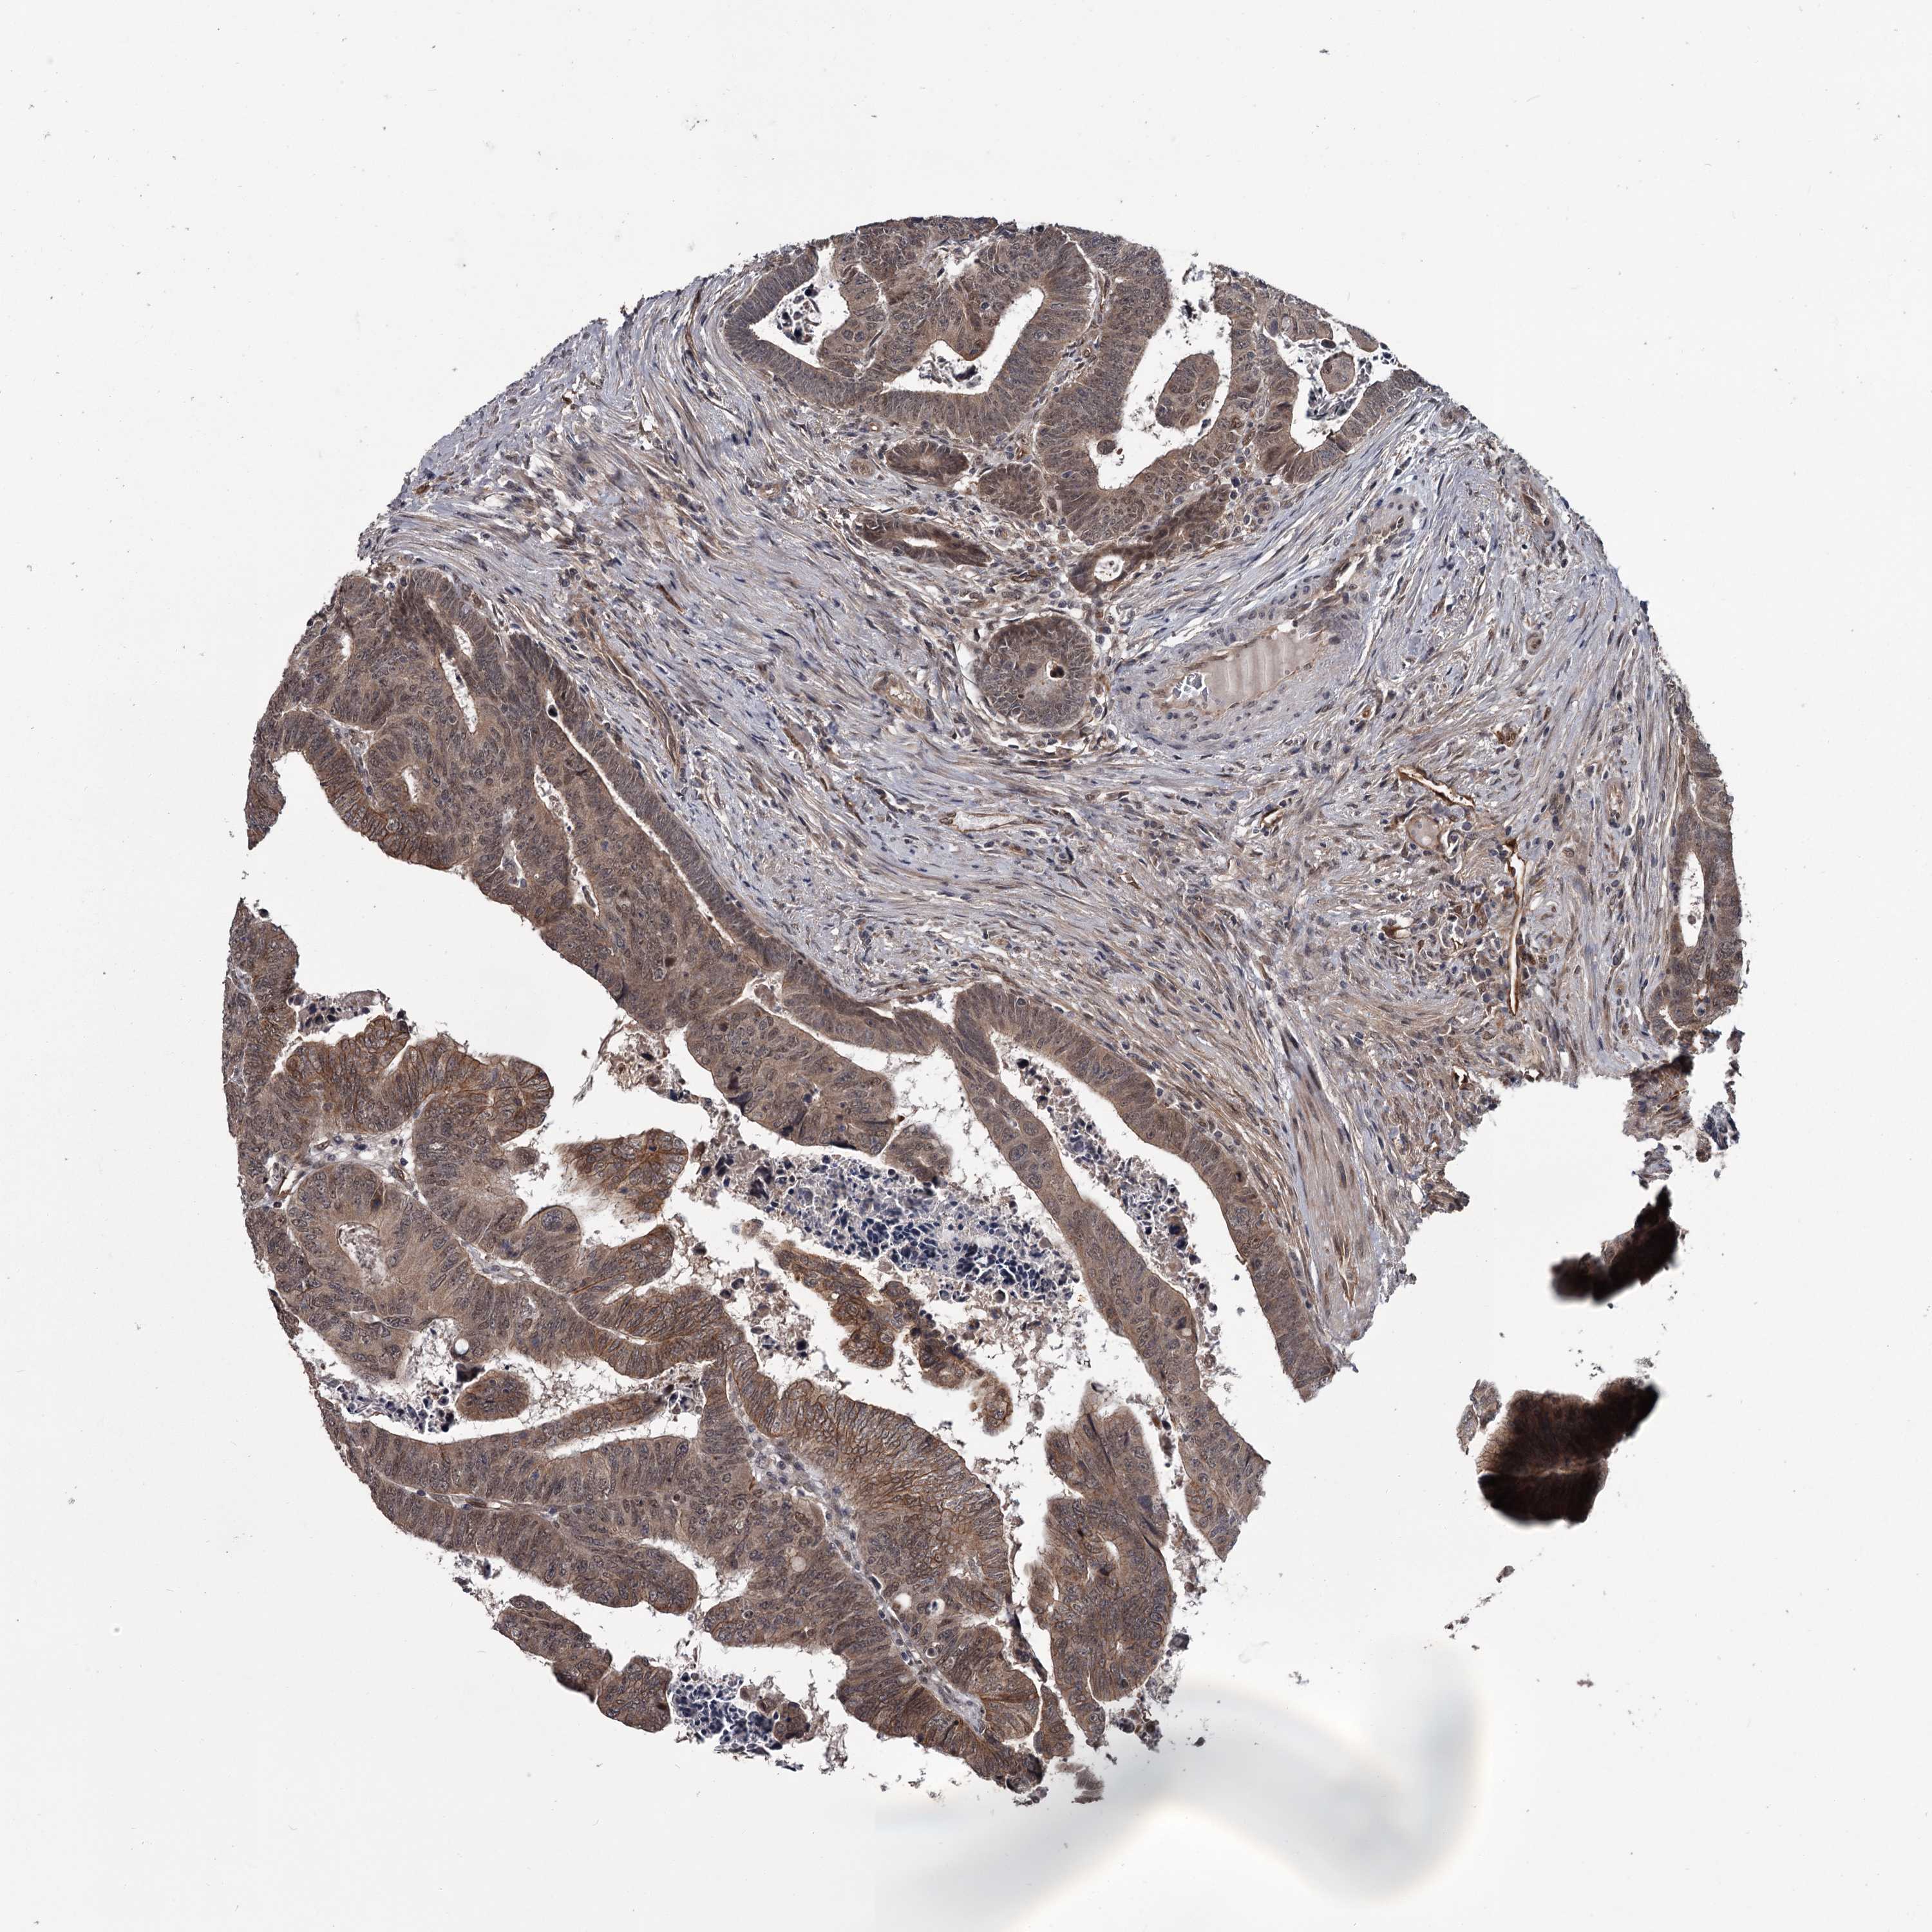

Colorectal cancer

Rectum adenocarcinoma